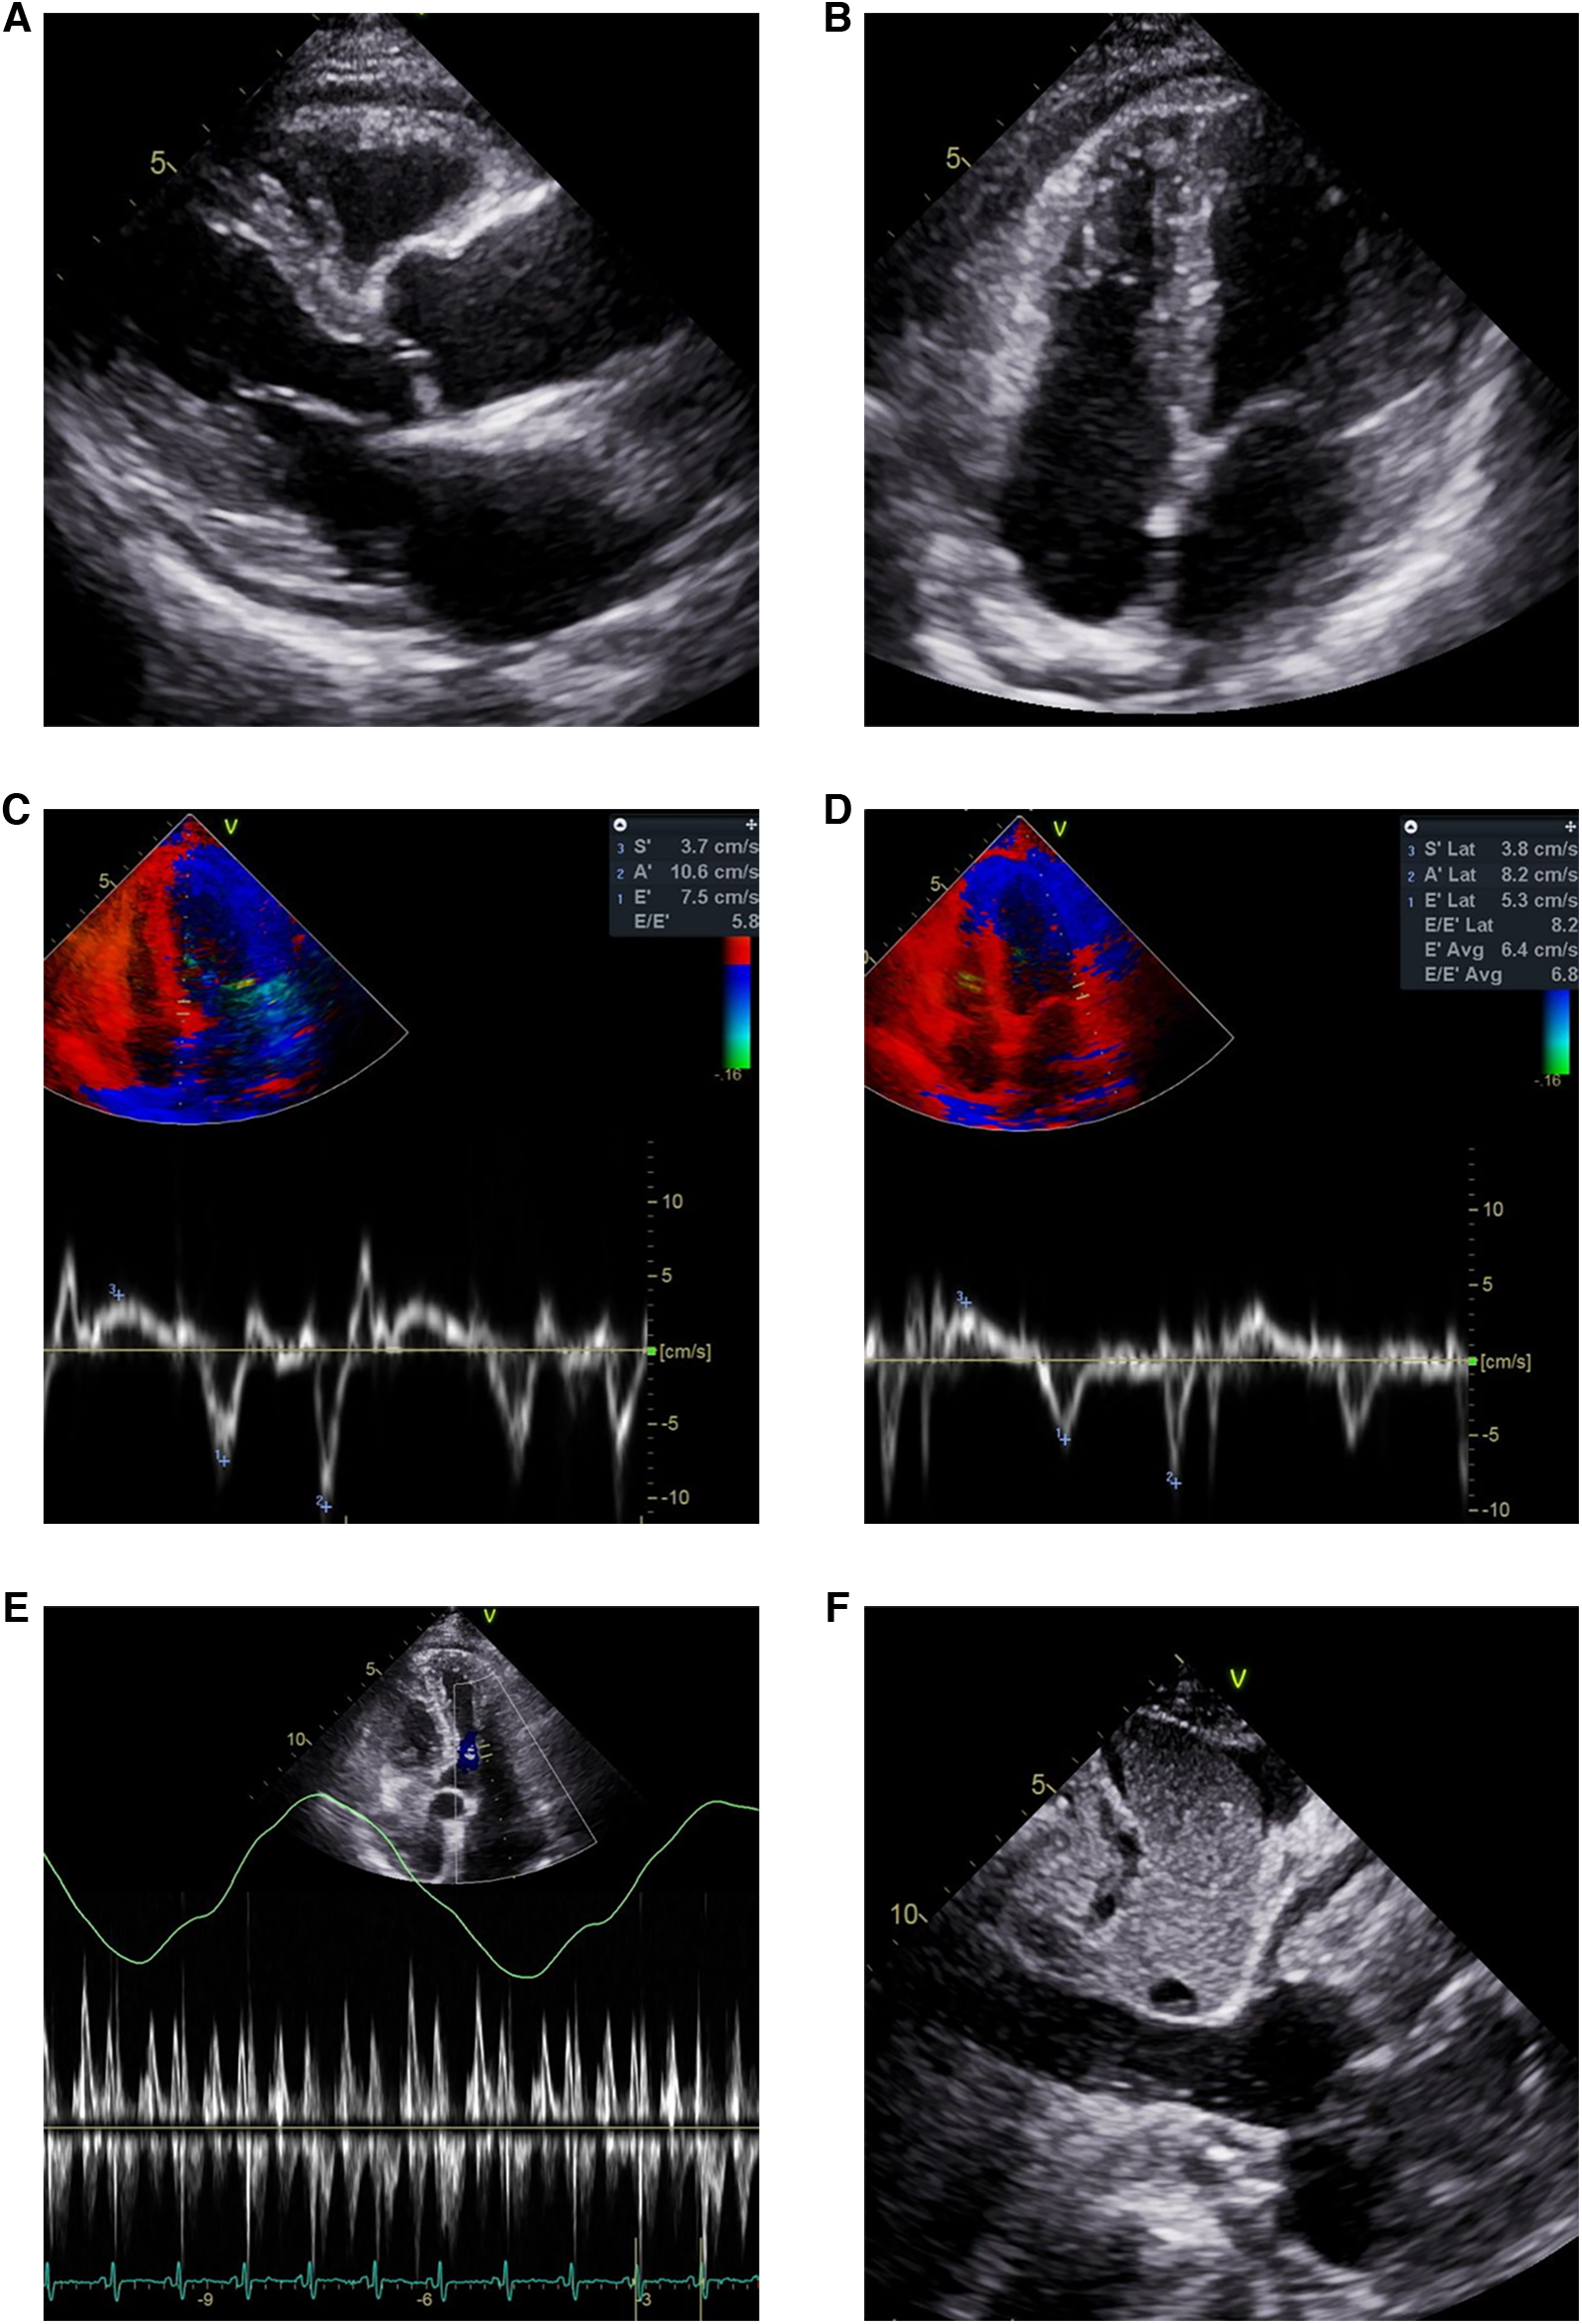

Figure 2

Echocardiogram showing pericardial effusion and constrictive physiology. Small amount of pericardial effusion and thickened pericardium in (A) parasternal long axis view and (B) modified 4-chamber view. Annulus inversus findings showing (D) decreased lateral e’ velocity compared to (C) septal e’ velocity. (E) Mitral inflow showing significant variations during respiration (F) Plethoric inferior vena cava during inspiration.

The patient visited the emergency room two weeks after discharge due to worsening abdominal distension and dyspnea. At presentation, his blood pressure was 95/60 mmHg and heart rate was 70 beats/min. His physical exam was remarkable for grade 2 pitting edema at the lower extremities, a marked jugular venous pulse, pericardial friction rub on ascultation, and a distended abdomen with shifting dullness. Laboratory findings included mildly elevated liver enzymes, with aspartate aminotransferase at 56 U/L and alanine aminotransferase at 64 U/L, and total bilirubin 1.3 mg/dl. A follow-up echocardiogram revealed pericardial thickening and adhesion at the apex and RV anterior wall, along with scanty pericardial effusion. Intraventricular septal bouncing and respiratory mitral and tricuspid valve inflow variability suggested constrictive pericarditis (Figure 2, Supplementary Video S1). Additionally, global hypokinesia resulted in a decreased LVEF of 39%. Large amounts of pleural effusion and ascites were apparent on CT scans of the chest and abdomen, the latter of which was identified as transudate by paracentesis (Figures 3A,B). Unfortunately, due to the patient's instability, right heart catheterization could not be performed.

Because pericardiectomy has the potential to provide relief of symptoms and improve prognosis, early recognition of CP is necessary. Patients with CAP in particular should be monitored using appropriate diagnostic testing, as this case illustrates. The typical patient will display signs and symptoms of right heart failure, with peripheral edema, abdominal distension, and elevated jugular venous pressure. Signs of hepatic dysfunction, such as elevated bilirubin and hypoalbuminemia, have been associated with increased mortality in CP patients undergoing pericardiectomy (2). Multimodality imaging techniques, with echocardiography as a first choice, are necessary for diagnosis. Characteristic echocardiographic findings of CP include diastolic septal bounce, plethoric IVC, and respiratory mitral and tricuspid inflow variation (9).